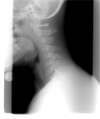

Les vertiges d’origine cervicale sont liés à un dysfonctionnement des vertèbres cervicales supérieures.

- Arthrose cervicale